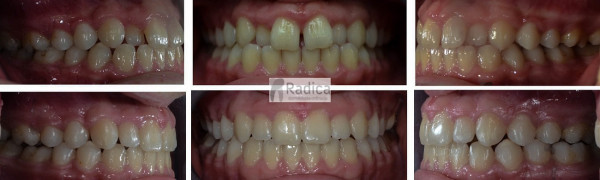

U galeriji slika su prikazani klinički slučajevi ovakvih odraslih pacijenta bilo da se radi samo o ortodontskoj terapiji ili predprotetskoj ortodonciji.

Kompresija –fiksni aparat bez ekstrakcije zuba

Slučaj 1